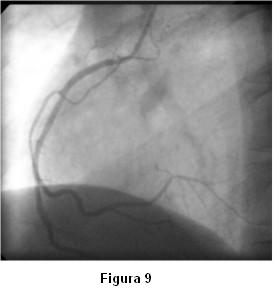

Con el planteo de síndrome coronario agudo de alto riesgo se solicita cineangiocoronariografía que muestra arterias coronarias sin lesiones significativas. Durante el estudio, al momento de cateterizar la coronaria izquierda, se observa severo vasoespasmo de las arterias descendente anterior, circunfleja y sus ramos secundarios (figura 4) con reproducción de los síntomas, que revierte espontáneamente en la siguiente inyección (figura 5).

Antes de la finalización del estudio de la coronaria izquierda reitera espasmo (figura 6) que mejora sin necesidad de administración de vasodilatadores (figuras 7 y 8).

Lo particular del caso presentado fue la aparición de severo espasmo difuso y multivaso de forma espontánea al momento de la cateterización de la arteria coronaria izquierda, sin provocación farmacológica y con reversión también espontánea.